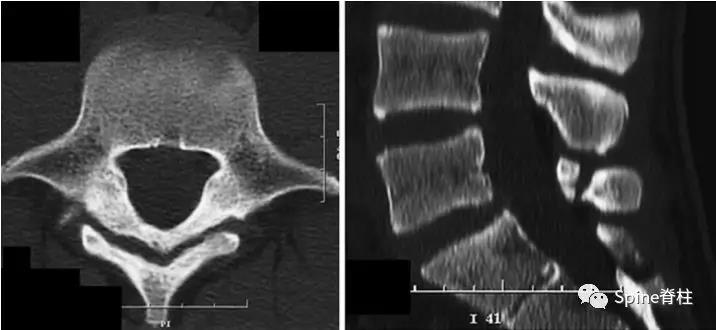

图:6个月复查可见右侧椎弓根裂已愈合(单箭头),但出现右侧峡部裂(双箭头)